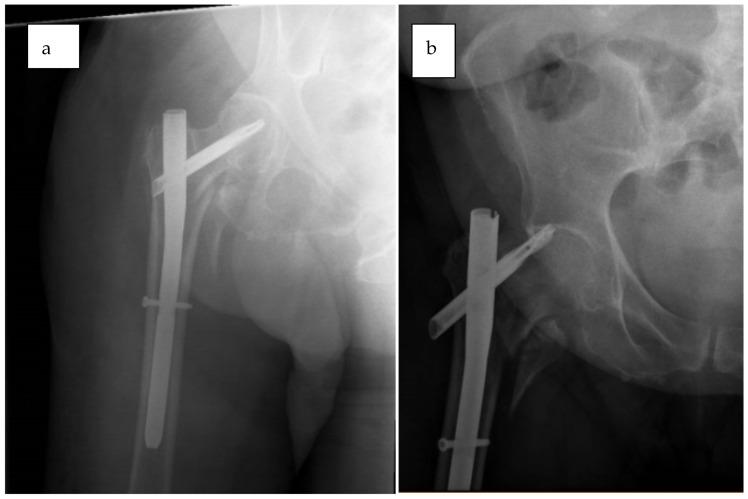

Intertrochanteric fractures in the elderly present complex challenges due to poor bone quality and comorbidities. Cephalomedullary (CM) nails offer biomechanical advantages that support early mobilization, yet complications such as cutout, implant failure, and malalignment persist. This review examines the effectiveness of CM nail fixation in geriatric extracapsular hip fractures and introduces the technique-a structured, mnemonic-based approach aimed at improving surgical outcomes and reducing common complications. stands for Reduce, Entry point, Screw, Compress, Unleash traction, and Enhance full-weight bearing. This six-step framework addresses the critical elements of fixation, including precise reduction, optimal entry point selection, central screw placement, controlled fracture compression, cautious traction management, and early mobilization. Case illustrations of frequent failure patterns underscore the practical application of the RESCUE technique. By following this systematic approach, surgeons can enhance construct stability, minimize failure risk, and promote functional recovery in elderly patients.

由于骨质不佳和合并症,老年患者的粗隆间骨折带来了复杂的挑战。髓内钉提供了支持早期活动的生物力学优势,但诸如穿出、植入物失败和对线不良等并发症仍然存在。本综述探讨了髓内钉固定治疗老年髋关节囊外骨折的有效性,并介绍了一种技术——一种基于结构化记忆法的方法,旨在改善手术效果并减少常见并发症。RESCUE代表复位、入点、螺钉、加压、释放牵引和增强全负重。这个六步框架涵盖了固定的关键要素,包括精确复位、最佳入点选择、中心螺钉置入、控制骨折加压、谨慎的牵引管理和早期活动。常见失败模式的病例说明强调了RESCUE技术的实际应用。通过遵循这种系统方法,外科医生可以增强内固定稳定性,将失败风险降至最低,并促进老年患者的功能恢复。